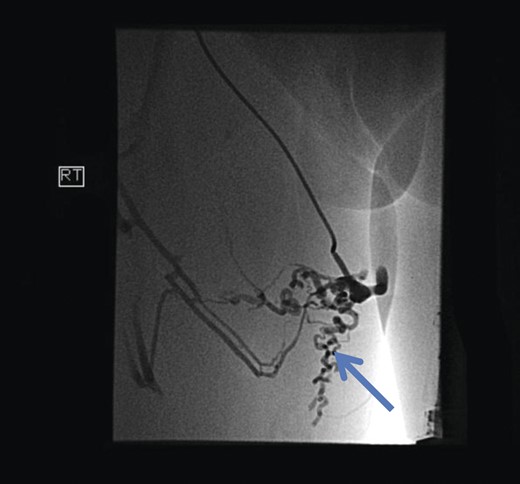

Initial investigations included duplex scan, followed by magnetic resonance scan. Duplex scanning demonstrated a competent sapheno-femoral (SFJ) and Sapheno-popliteal (SPJ) junctions bilaterally; however, did raise suspicion of a pelvic origin of the vulval varices with congested pelvic veins. Magnetic resonance venogram aided the diagnosis by demonstrating the communication of the vulval varices to the upper thigh veins with contribution from the internal iliac vein. In this case there was no evidence of ovarian varices (Fig. 1). Catheter venography was unable to confirm the contributing vein with certainty but computed pelvic venography showed a likely connection through the superficial external pudendal vein (Fig. 2).

Magnetic resonance venogram showing communication of thigh veins to vulval varices (blue arrow).